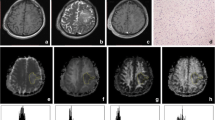

Diffusion spectrum imaging was performed in 122 meningiomas (30 males, 13–84 years), which were divided into 31 high-grade meningiomas (HGMs, grades 2 and 3) and 91 low-grade meningiomas (LGMs, grade 1). The histogram features of multiple diffusion metrics obtained from diffusion tensor imaging (DTI), diffusion kurtosis imaging (DKI), mean apparent propagator (MAP), and neurite orientation dispersion and density imaging (NODDI) in the solid tumours were analysed. All values between the two groups were compared with the Man-Whitney U test. Logistic regression analysis was applied to predict meningioma grade. The correlation between diffusion metrics and Ki-67 index was analysed.

The DKI_AK (axial kurtosis) maximum, DKI_AK range, MAP_RTPP (return-to-plane probability) maximum, MAP_RTPP range, NODDI_ICVF (intracellular volume fraction) range, and NODDI_ICVF maximum values were lower (p < 0.0001), whilst the DTI_MD (mean diffusivity) minimum values were higher in LGMs than those in HGMs (p < 0.001). Amongst the DTI, DKI, MAP, NODDI, and combined diffusion models, no significant differences were found in areas under the receiver operating characteristic curves (AUCs) for grading meningiomas (AUCs, 0.75, 0.75, 0.80, 0.79, and 0.86, respectively; all corrected p > 0.05, Bonferroni correction). Significant but weak positive correlations were found between the Ki-67 index and DKI, MAP, and NODDI metrics (r = 0.26–0.34, all p < 0.05).

Whole tumour histogram analyses of the multiple diffusion metrics from four diffusion models are promising methods in grading meningiomas. The DTI model has similar diagnostic performance compared with advanced diffusion models.